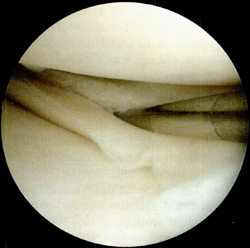

Типовий розрив меніска з вивихом типу «ручка лійки» на схемі і через артроскоп

Якщо такі епізоди повторюються, виникає необхідність в операції з видалення розірваної частини меніска. Це нескладна і безпечна операція, яку виконують через проколи шкіри під контролем артроскопа - тонкого оптоволоконного зонда діаметром близько 0,5 см, до якого приєднані відеокамера і джерело світла.

Під контролем відеозображення на моніторі відірвану частину меніска відсікають і видаляють.